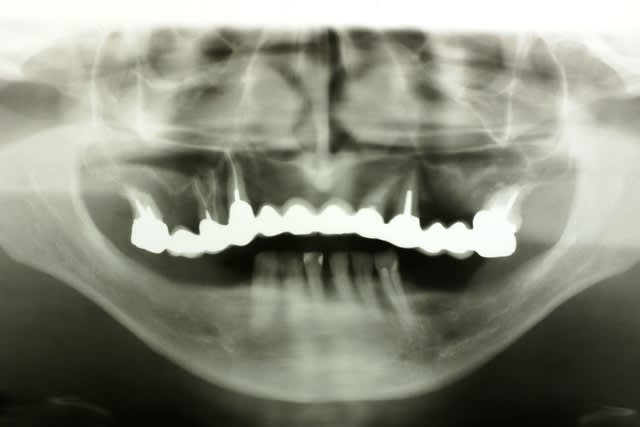

Bon un petit travail réalisé à main levée et sans aucune forme de guide...

Avec un pano de m..... ;)

çà c'est clair!!!(contrairement à la pano...)

C'est plus de la biologie, c'est de la mécanique!

Mais vu la quantité d'os disponible, il ne restait pas 36 solutions. Pas facile comme cas.

Ca tiendra certainement, mais a la pano c'est pas beau, surtout avec cette qualité.

Par contre, en bas la barre.. J'espère que la patiente aura une bonne maintenance.